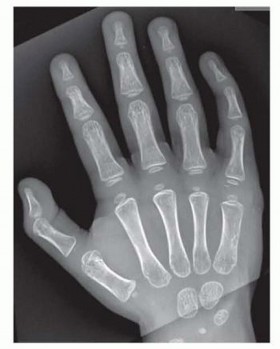

Standard radiographs (three views—anteroposterior, lateral, and oblique) of the hand and affected digit are sufficient to determine the area of involvement (FIG 2).Advanced imaging such as magnetic resonance imaging (MRI) and computed tomography (CT) is rarely needed.

FIG 2• Preoperative radiograph of the patient in FIG 1 with type A postaxial polydactyly, depicting the bifacet metacarpal head.